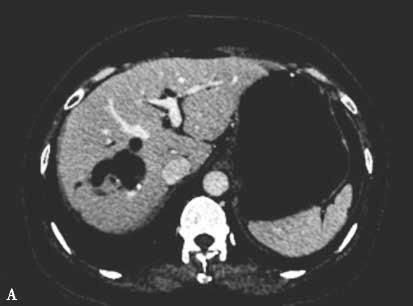

图2-5-1 采用不同栓塞材料实施PVE

A、a.弹簧微钢圈栓塞门静脉右支;

A.PVE术前CT;a.PVE术前三维可视化重建;

B.门静脉右支行弹簧微钢圈联合NCBA栓塞,术后2周复查CT见弹簧微钢圈移位至肝左外叶门静脉末梢支,肝左内叶见NCBA分布;b.PVE术后三维可视化重建,NCBA自门静脉右支移位至门静脉左内叶分支。